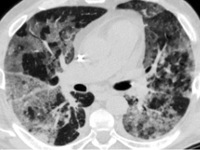

Так вот, пневмония легкого у человека — это такое инфекционное воспаление легочной ткани. Мешочки, из которых состоят легкие человека, у здорового человека нормально наполняются воздухом при дыхании и в них обычным образом происходит газообмен кислорода и углекислого газа.

При наступлении пневмонии эти самые мешочки легкого заполнены жидкостью воспалительной. Это затрудняет этот самый газообмен и препятствует поступление кислорода во все органы тела человека.

Но самое важное исследование при подозрении на воспаление легких — рентгенография. В некоторых случаях, когда пораженный локус легких располагается ближе к диафрагме, потребуется КТ.